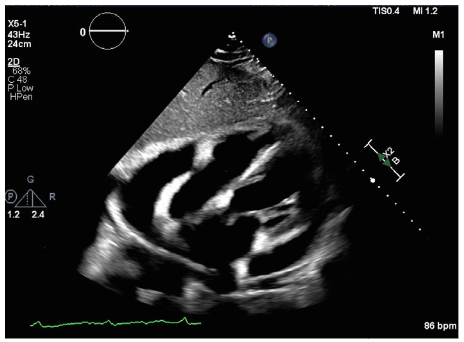

出院1周后复查心脏超声提示大量心包积液,伴早期心包填塞表现(右心房舒张期塌陷)(图 1)。紧急行心包穿刺术,引流出930ml琥珀色液体,送检生化及细胞学分析(表1)。结果显示:红细胞13,000/μL(正常参考值<2000/μL),总核细胞数7074/μL(正常参考值<1000/μL),中性粒细胞61%(正常参考值0%-1%),细胞学提示恶性细胞(DLBCL)。

图1. 超声心动图图像显示一个大的环形心包填塞,伴有早期填塞生理学(右心房舒张期塌陷)